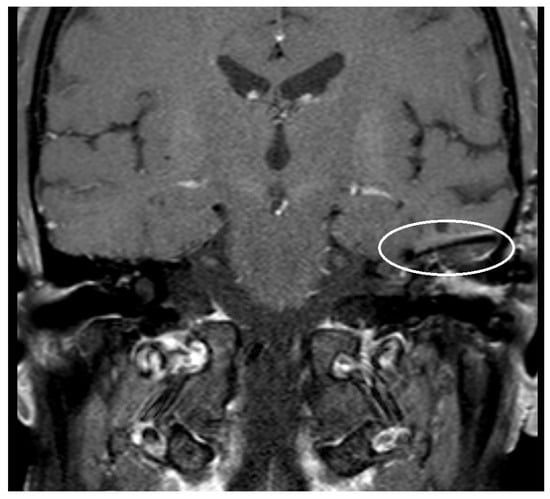

| PORP | 2.0 mm | 3.1 mm | 5.4 mm |

| TORP | 3.6 mm | 4.7 mm | 7.2 mm |

| Mesh | 0.1 mm | 3.6 mm | 5.8 mm |